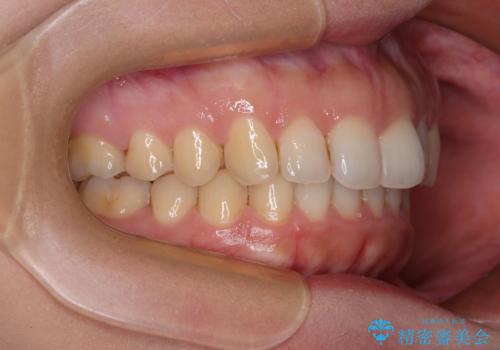

インビザライン矯正で前歯のデコボコを改善

骨格的に下顎骨が左にずれており、上下の正中一致は困難ではありましたが、IPR(歯と歯の間を削る)や後方への移動など組み合わせて、できる限り改善しました。

インビザラインはマウスピースを外している時間が長いと、長期間使用しても前歯のデコボコはあまり改善されません。こちらの患者様は治療期間が長くなり、装着時間が短くなってしまったことで、気になる部分の改善により長期間を要するようになってしまいました。